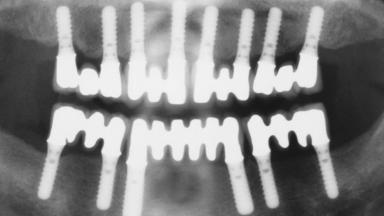

Immediate Loading of Eight Implants in the Maxilla and Six Implants in the Mandible and Final Restoration with Three-Unit and Four-Unit FDPs

# of Implants 14

Type of Implants One-Piece

Surgical SAC classification

SAC Level Complex

Defining Characteristics Fully edentulous upper jaw to be rehabilitated with four or more implants

Modality 6+ implants with immediate loading